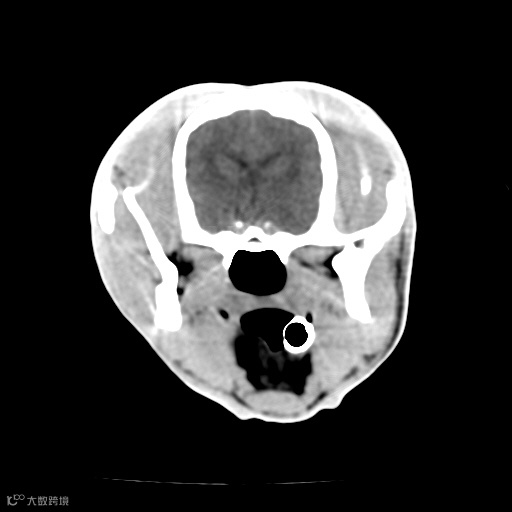

脑白质/灰质清晰

由于扫描参数、金属物体或运动等因素引起的图像畸变。评估伪影时, 应注意图像中是否存在条纹状、环状或阴影状的异常结构,以及其对图像质量和解剖结构的影响。

金属伪影